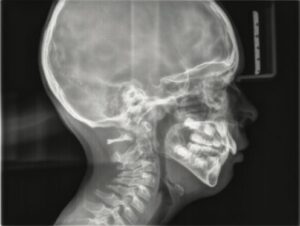

In this compelling article, Dr. Batoon discusses the challenges and solutions in treating children with sleep-related issues. She presents case studies that not only highlight the importance of an integrative approach to dentistry but also showcase the effectiveness of LightScalpel CO2 lasers in treatment protocols.